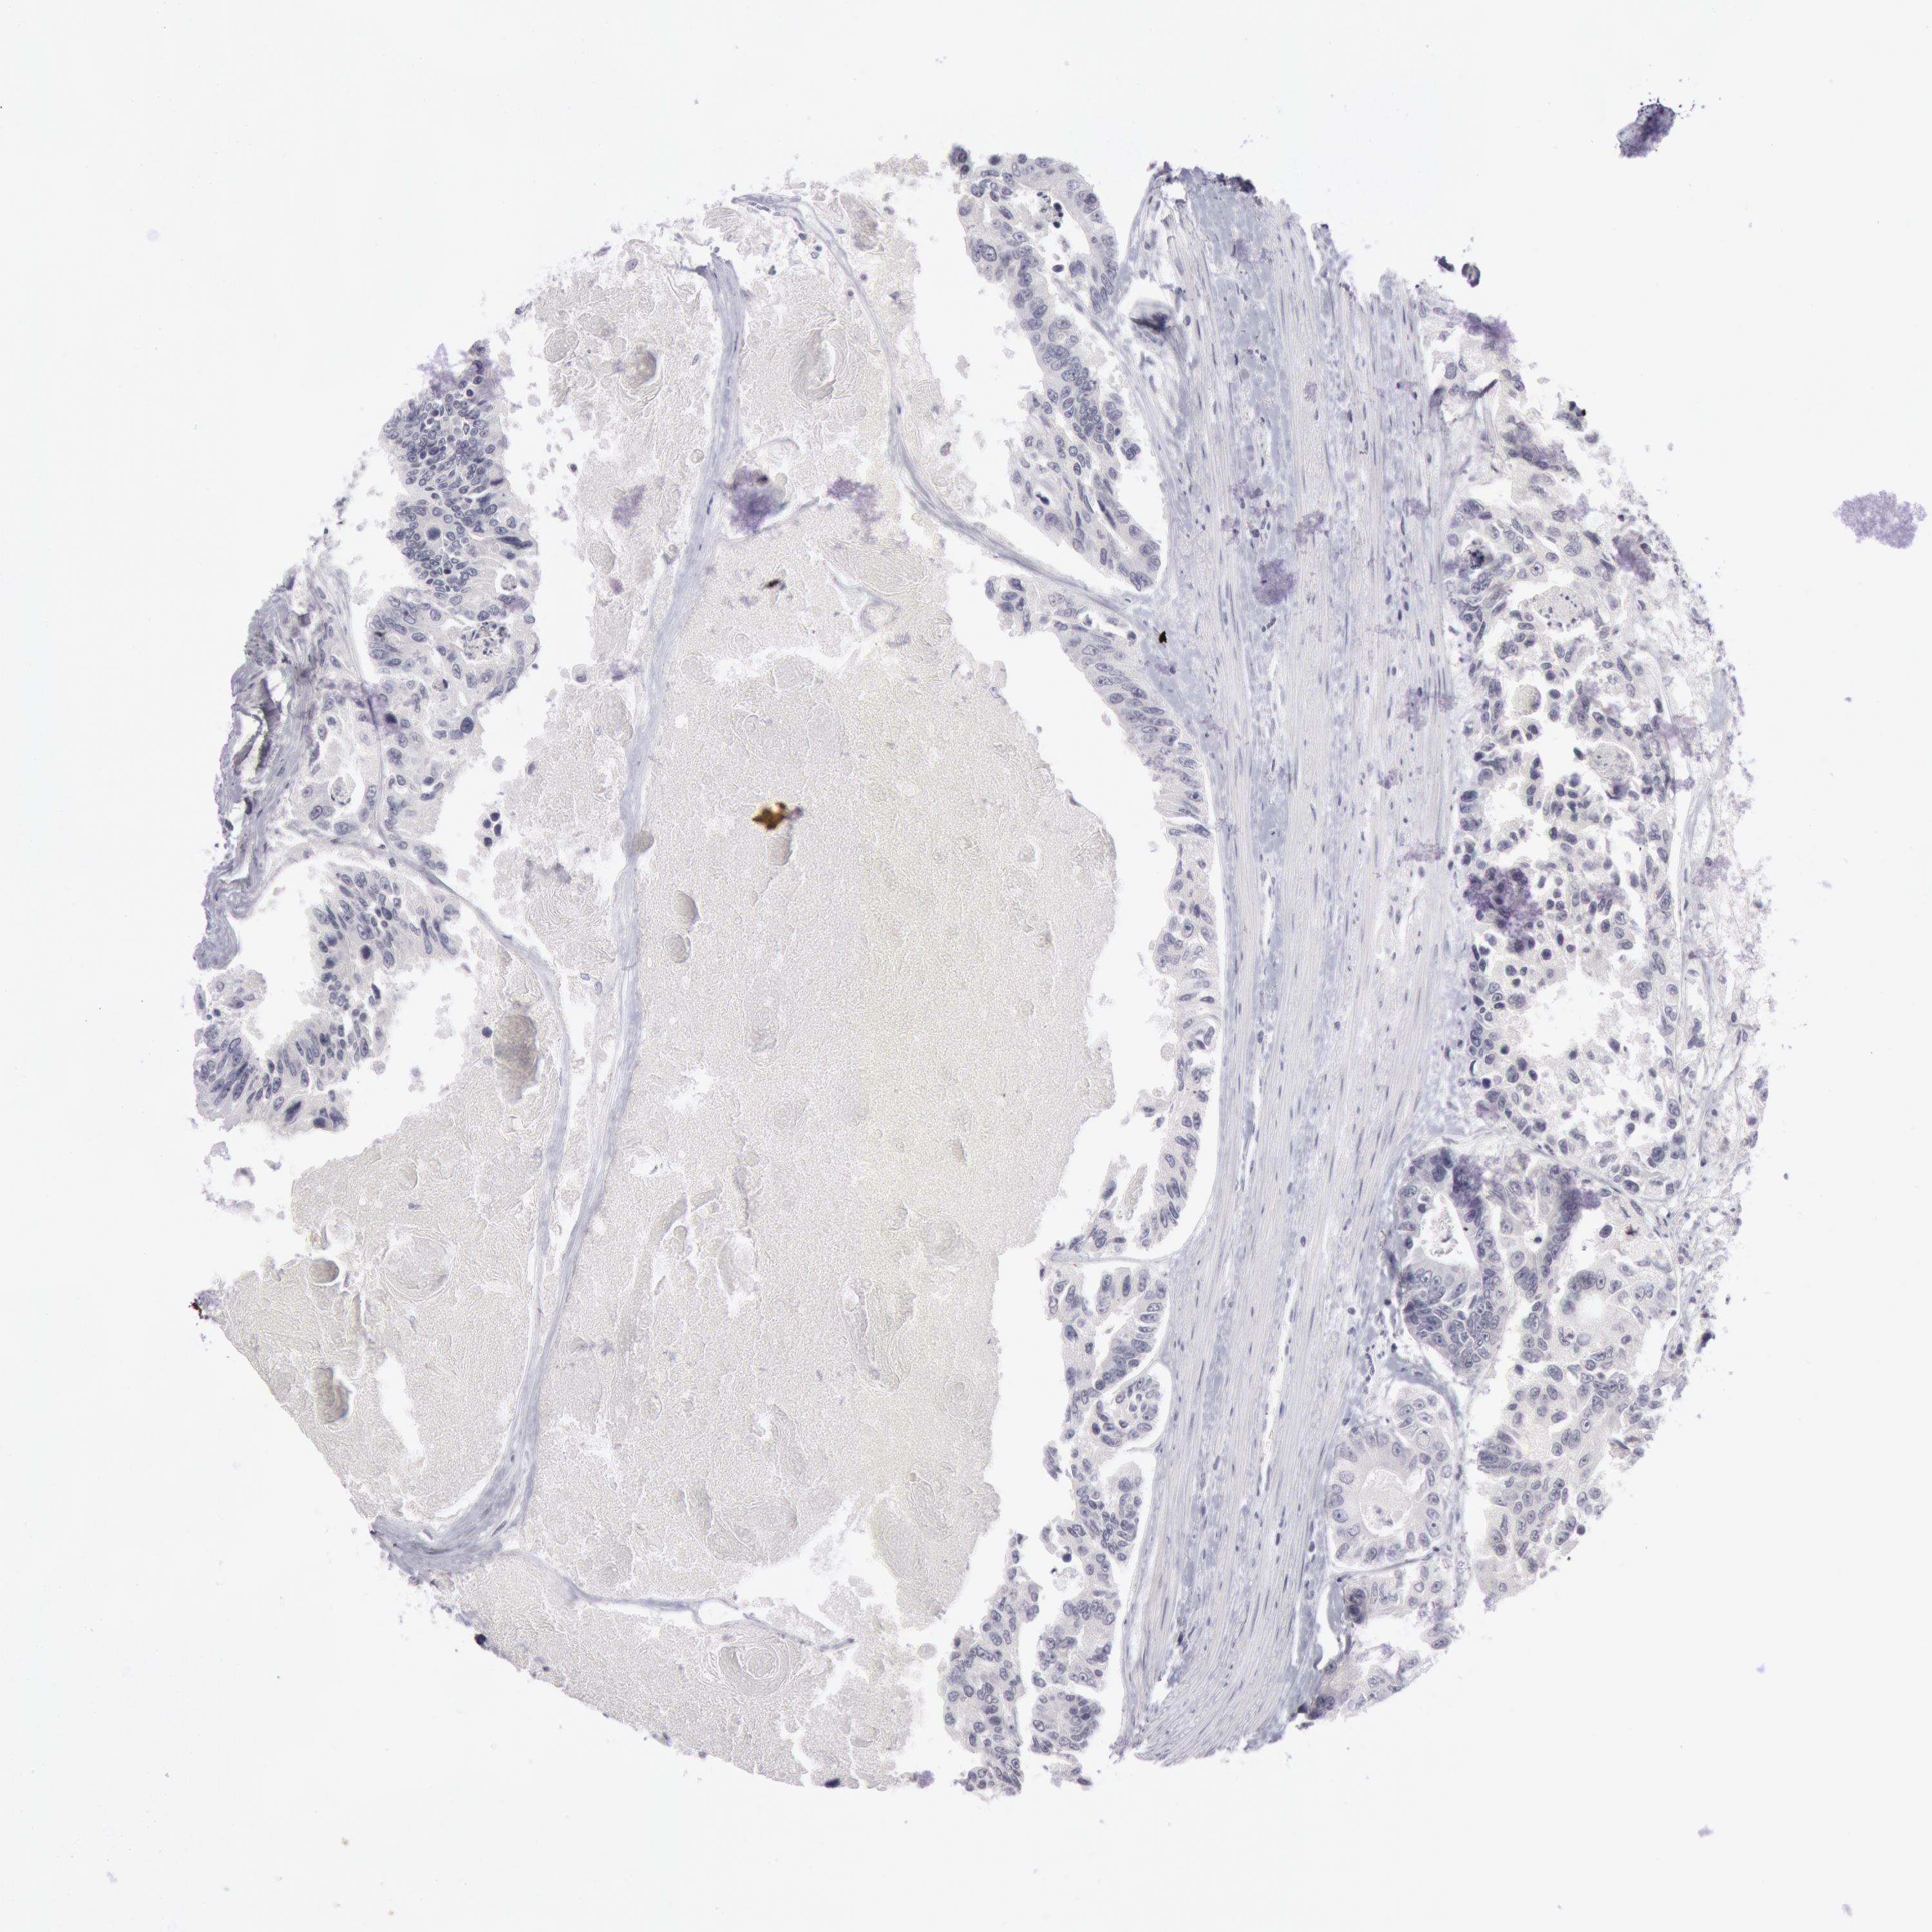

CANCER COLORECTAL CANCER Show tissue menu

Colorectal cancer

Human cancer

Colon adenocarcinoma

COLON ADENOCARCINOMA (TCGA) - Interactive survival scatter ploti

The Survival Scatter plot shows the clinical status (i.e. dead or alive) for all individuals in the patient cohort, based on the same data that underlies the corresponding Kaplan-Meier plots. Patients that are alive at last time for follow-up are shown in blue and patients who have died during the study are shown in red.

The x-axis shows the expression levels (FPKM) of the investigated gene in the tumor tissue at the time of diagnosis. The y-axis shows the follow-up time after diagnosis (years). Both axes are complimented with kernel density curves demonstrating the data density over the axes. The top density plot shows the expression levels (FPKM) distribution among dead (red) and alive patients (blue). The right density plot shows the data density of the survived years of dead patients with high and low expression levels respectively, stratified using the cutoff indicated by the vertical dashed line through the Survival Scatter plot. This cutoff is automatically defined based on the FPKM cutoff that minimizes the p-score. The cutoff can be changed by dragging the vertical line or by entering a cutoff value in the square labeled "Current cut-off".

Under the Survival Scatter plot the p-score landscape (black curve; left axis) is shown together with dead median separation (red curve; right axis). Dead median separation is the difference in median mRNA expression between patients who have died with high and low expression, respectively. It is calculated as follows: median FPKM expression of dead patients with high expression - median FPKM expression of dead patients with low expression. This is intended to aid the user in visually exploring custom cutoffs and the associated p-scores and dead median separation.

Individual patient data is displayed and can be filtered by clicking on one or more of the category buttons on the top of the page. Categories describing expression level and patient information include: high, low, alive, dead, female, male and tumor stages. The scale of the x-axis can be toggled between linear and log-scale by clicking on the "x log" button. Mouse-over function shows TCGA ID, patient information and mRNA expression (FPKM) for each patient.

& Survival analysisi

Kaplan-Meier plots summarize results from analysis of correlation between mRNA expression level and patient survival. Patients were divided based on level of expression into one of the two groups "low" (under cut off) or "high" (over cut off). X-axis shows time for survival (years) and y-axis shows the probability of survival, where 1.0 corresponds to 100 percent.

KRT16 is not prognostic in Colon Adenocarcinoma (TCGA)

Best expression cut offi

: 0.32

P scorei

N/A

TCGA RNA samplesi

RNA-seq data is reported as average FPKM (number Fragments Per Kilobase of exon per Million reads), generated by the The Cancer Genome Atlas (TCGA) .

Normal distribution across the dataset is visualized with box plots, shown as median and 25th and 75th percentiles. Points are displayed as outliers if they are above or below 1.5 times the interquartile range. FPKM values of the individual samples are presented next to the box plot.

Average pTPM 6.2

Number of samples 254